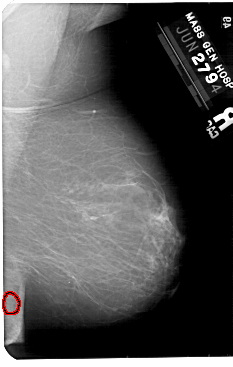

A_1561_1.RIGHT_MLO

RIGHT_MLO LINES 5491 PIXELS_PER_LINE 3481 BITS_PER_PIXEL 12 RESOLUTION 43.5 OVERLAY

FILE: A_1561_1.RIGHT_MLO.OVERLAY

TOTAL_ABNORMALITIES 1

ABNORMALITY 1

LESION_TYPE CALCIFICATION TYPE PLEOMORPHIC DISTRIBUTION CLUSTERED

ASSESSMENT 3

SUBTLETY 3

PATHOLOGY BENIGN

TOTAL_OUTLINES 1